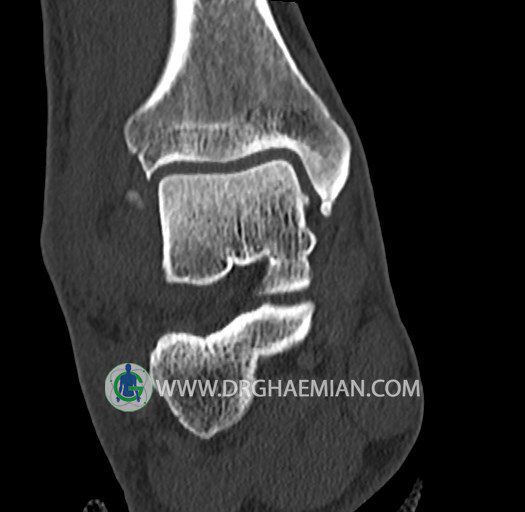

سی تی اسکن پا تصاویری عرضی از پا ایجاد می کند. این روش تصویربرداری از اشعه ایکس برای ایجاد تصاویر ایجاد می شود. در این کیس هيپرپلازي مچ پا، تورم نسج نرم و استئوفیت در مچ پا بیمار مشاهده می شود.

سي تي اسکن مچ پاي راست (مولتي ديدکتور 16 با مقاطع ظريف و بازسازي هاي ساژيتال و کرونال و 3D):

– تورم نسج نرمي در اطراف قوزک خارجي پاي راست

– Cortical Fx در قسمت خلفي اپيفيز ديستال تيبيا و

– هيپرپلازي lateral tubercle در تالوس ( stieda process ) همراه با اوستئوفيت در لبه

مديال تيبيا و تالوس